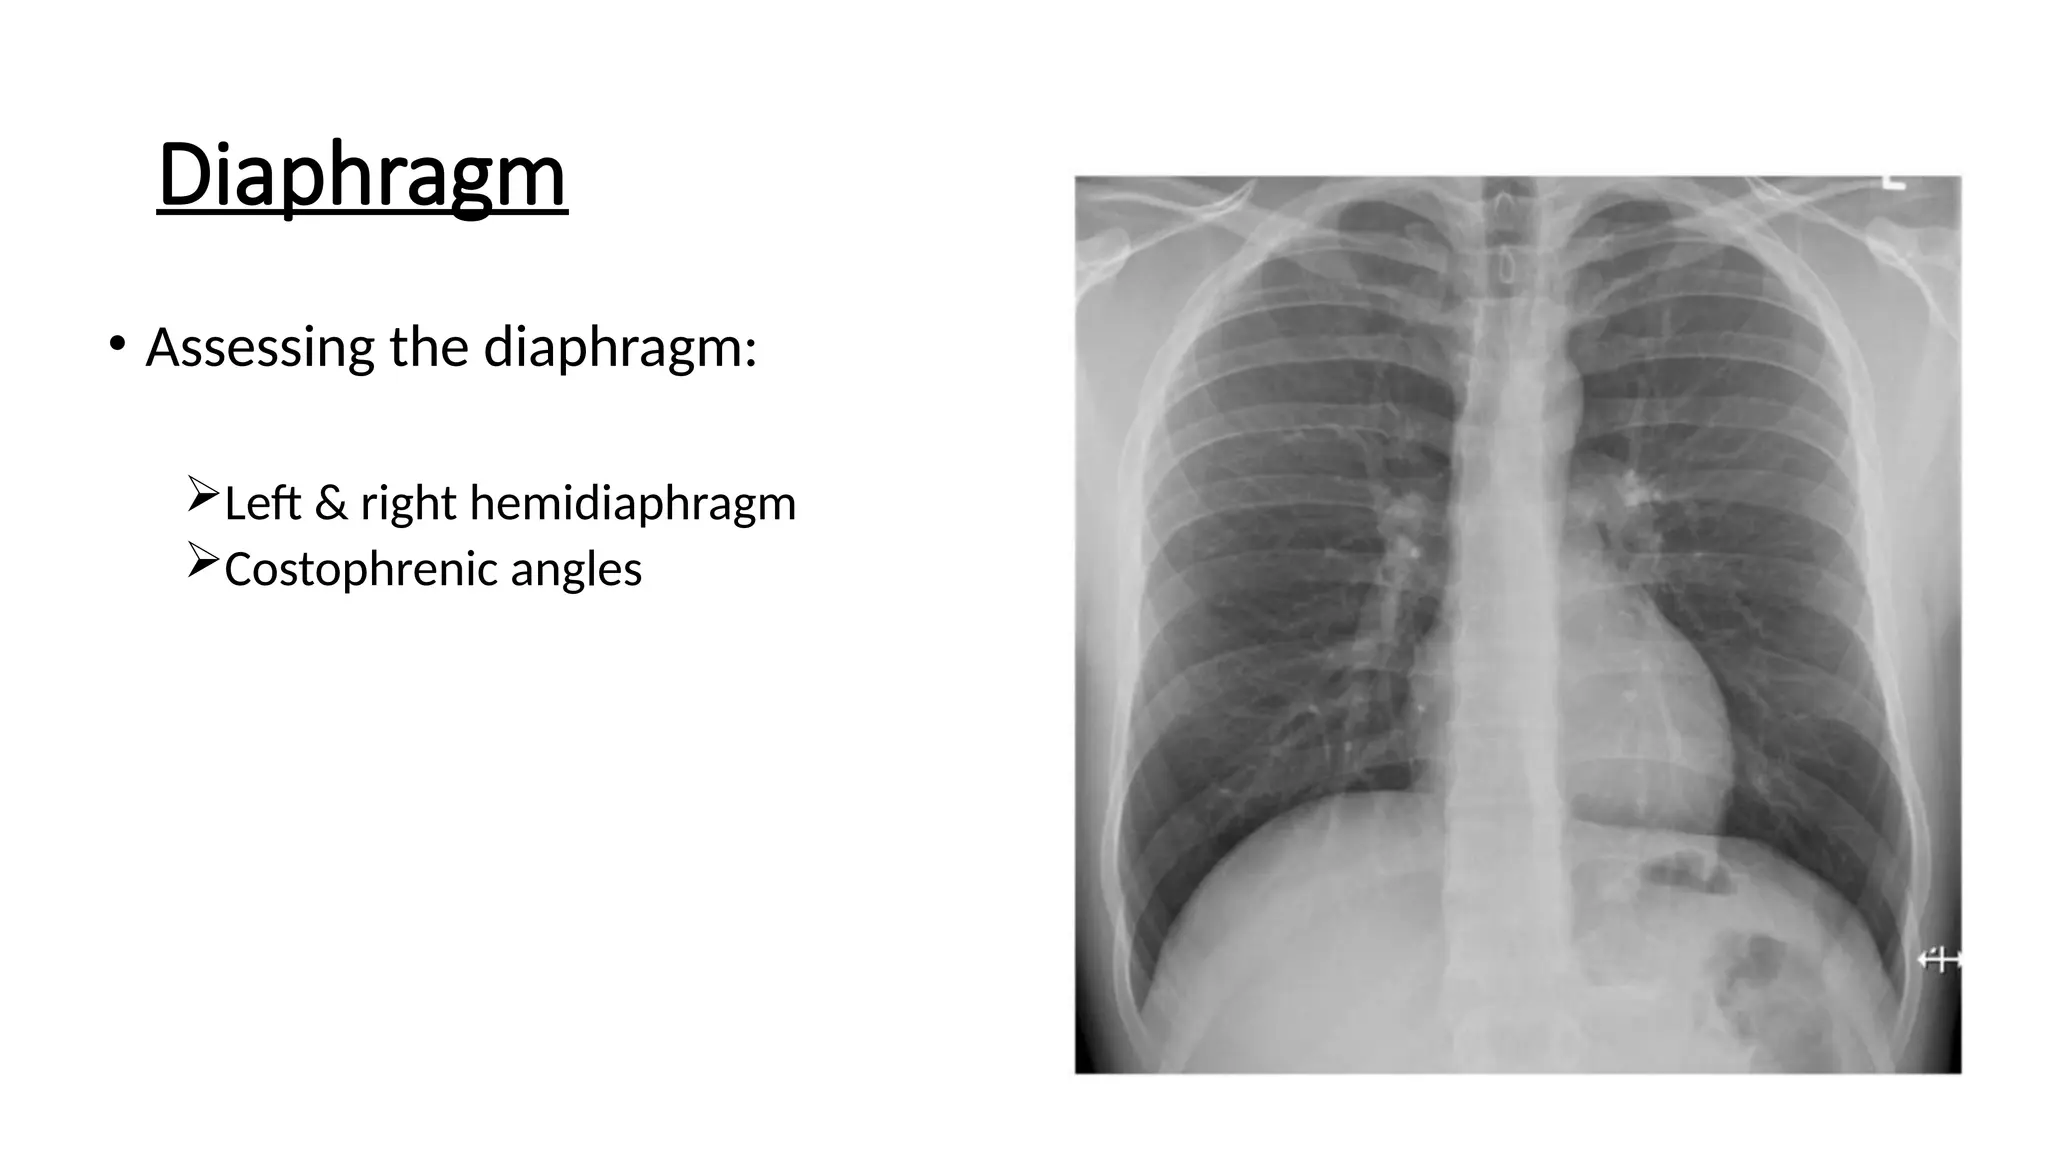

Diaphragm

• Assessing the diaphragm:

Left & right hemidiaphragm

Costophrenic angles